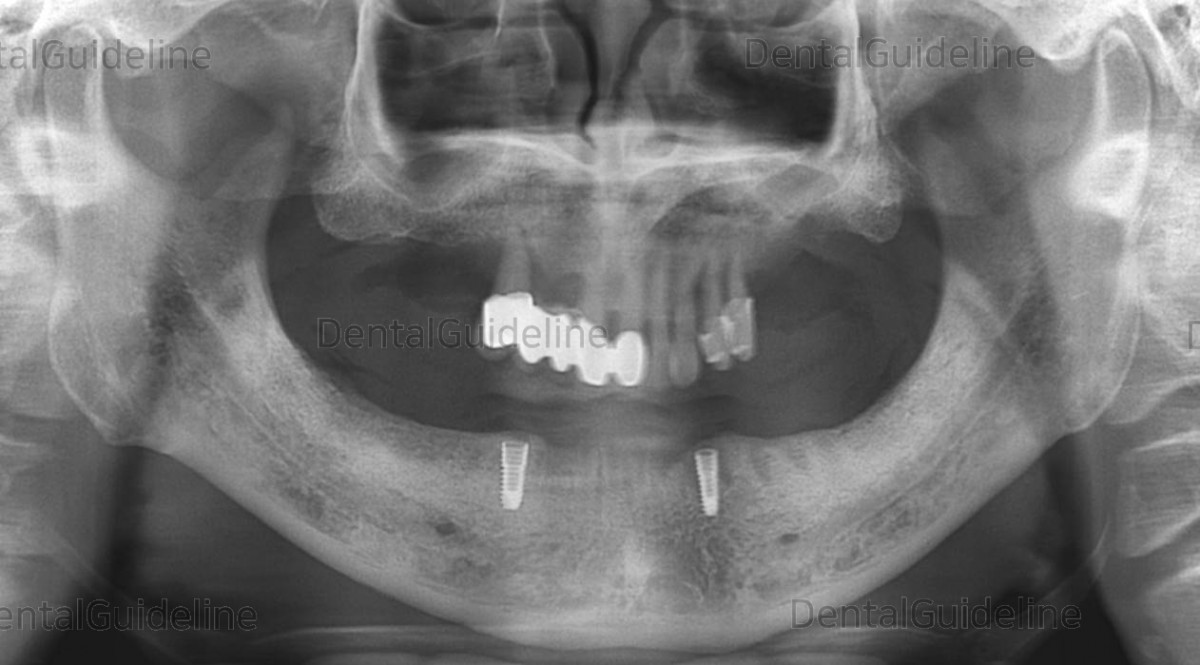

Edentulous mandible

Dentures were manufactured for edentulous patients, then it was replicated for implant surgical guide.

2 implants were placed using the surgical guide.